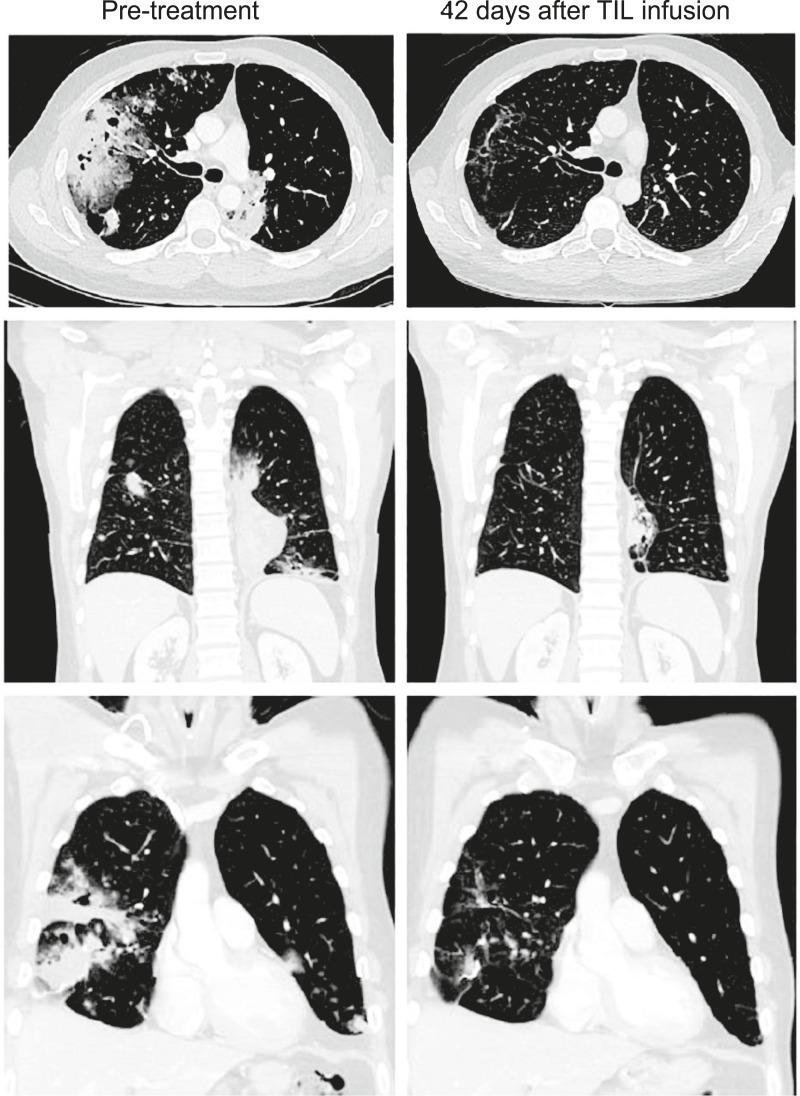

In this phase 2 multicenter study, we evaluated the efficacy and safety of lifileucel (LN-145), an autologous tumor-infiltrating lymphocyte cell therapy, in patients with metastatic non-small cell lung cancer (mNSCLC) who had received prior immunotherapy and progressed on their most recent therapy. The median number of prior systemic therapies was 2 (range, 1-6). Lifileucel was successfully manufactured using tumor tissue from different anatomic sites, predominantly lung. The objective response rate was 21.4% (6/28). Responses occurred in tumors with profiles typically resistant to immunotherapy, such as PD-L1-negative, low tumor mutational burden, and STK11 mutation. Two responses were ongoing at the time of data cutoff, including one complete metabolic response in a PD-L1-negative tumor. Adverse events were generally as expected and manageable. Two patients died of treatment-emergent adverse events: cardiac failure and multiple organ failure. Lifileucel is a potential treatment option for patients with mNSCLC refractory to prior therapy. Significance: Autologous tumor-infiltrating lymphocyte therapy lifileucel was administered to 28 patients with heavily pretreated metastatic non-small cell lung cancer (mNSCLC). Responses were observed in patients with driver mutations, and various tumor mutational burdens and PD-L1 expression, potentially addressing an unmet medical need in patients with mNSCLC refractory to prior therapy. See related commentary by Lotze et al., p. 1366.

在这项 2 期多中心研究中,我们评估了 lifileucel(LN-145),一种自体肿瘤浸润淋巴细胞细胞疗法,在先前接受过免疫治疗且最近的治疗进展的转移性非小细胞肺癌(mNSCLC)患者中的疗效和安全性。先前系统治疗的中位数为 2(范围,1-6)。使用来自不同解剖部位的肿瘤组织成功制造了 lifileucel,主要是肺。客观缓解率为 21.4%(28 例中有 6 例)。在免疫治疗通常耐药的肿瘤中发生了反应,例如 PD-L1 阴性、低肿瘤突变负担和 STK11 突变。数据截止时,有 2 个缓解仍在持续,包括 PD-L1 阴性肿瘤中的一个完全代谢缓解。不良事件通常如预期的那样且可管理。两名患者因治疗出现的不良事件死亡:心力衰竭和多器官衰竭。Lifileucel 是先前治疗难治性 mNSCLC 患者的潜在治疗选择。意义:自体肿瘤浸润淋巴细胞疗法 lifileucel 被施用于 28 名先前接受过大量治疗的转移性非小细胞肺癌(mNSCLC)患者。在有驱动突变的患者中观察到了反应,并且有各种肿瘤突变负担和 PD-L1 表达,这可能满足了先前治疗难治性 mNSCLC 患者的未满足的医疗需求。见相关评论 Lotze 等人,第 1366 页。